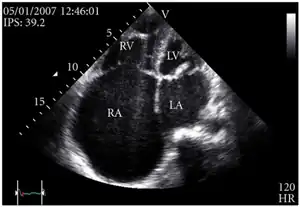

Definitive diagnosis is made by echocardiogram, which is capable of measuring both the presence and the severity of the TR, as well as right ventricular dimensions and systolic pressures.[12]

Transthoracic echo: enlargement of the right atrium in TR and mitral valve disease

Echocardiogram: severe TR